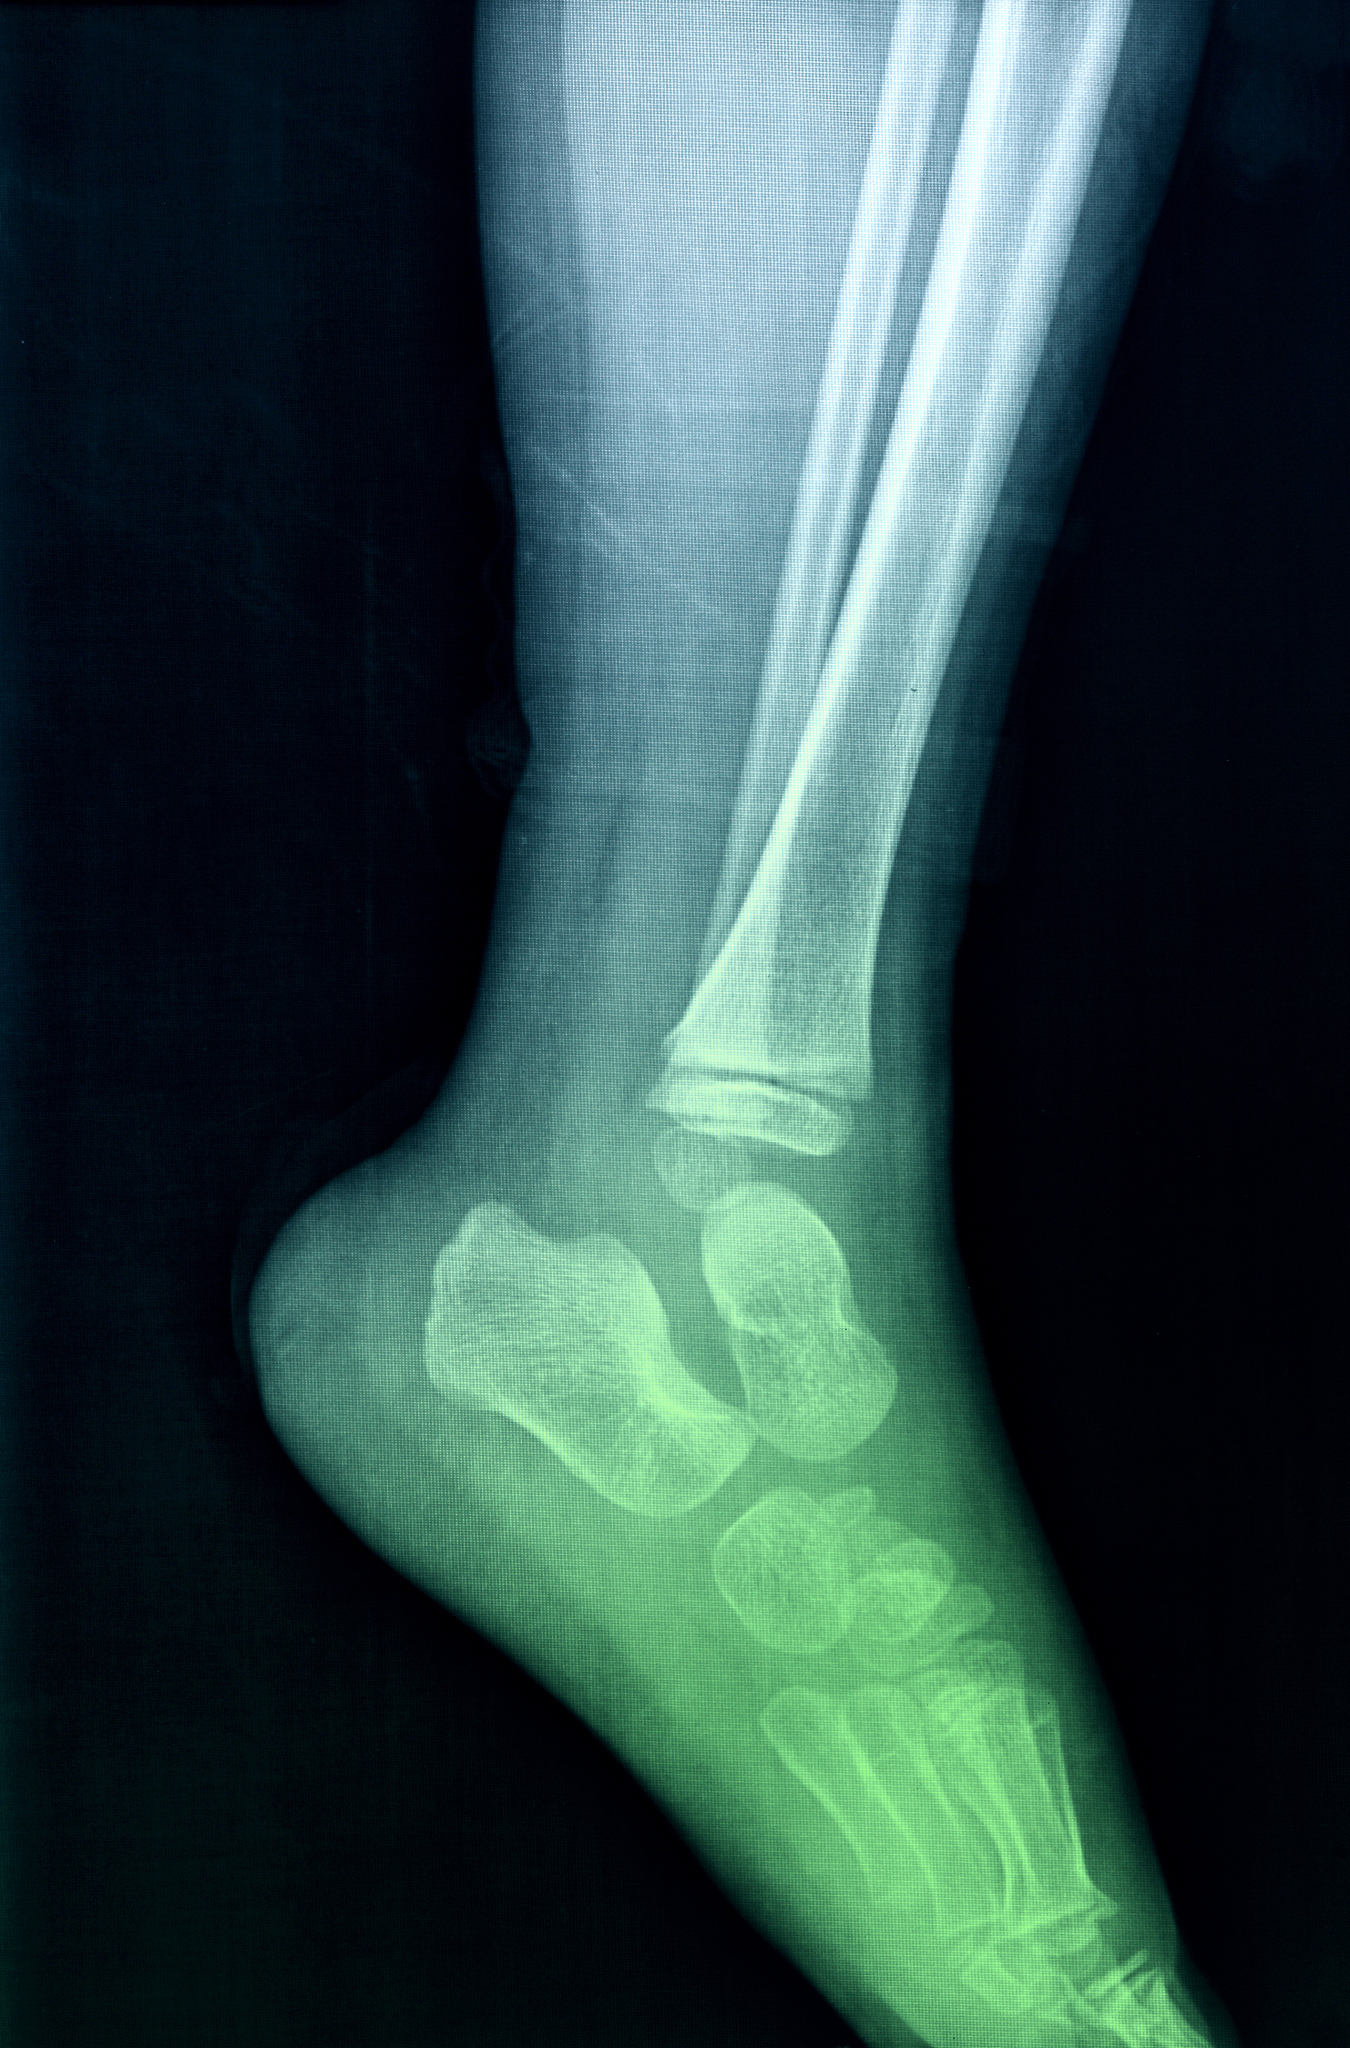

生理性突出无需处理;病理性突出需就医检查(如X光片),明确原因后治疗,如骨赘需对症止痛,囊肿可手术切除。